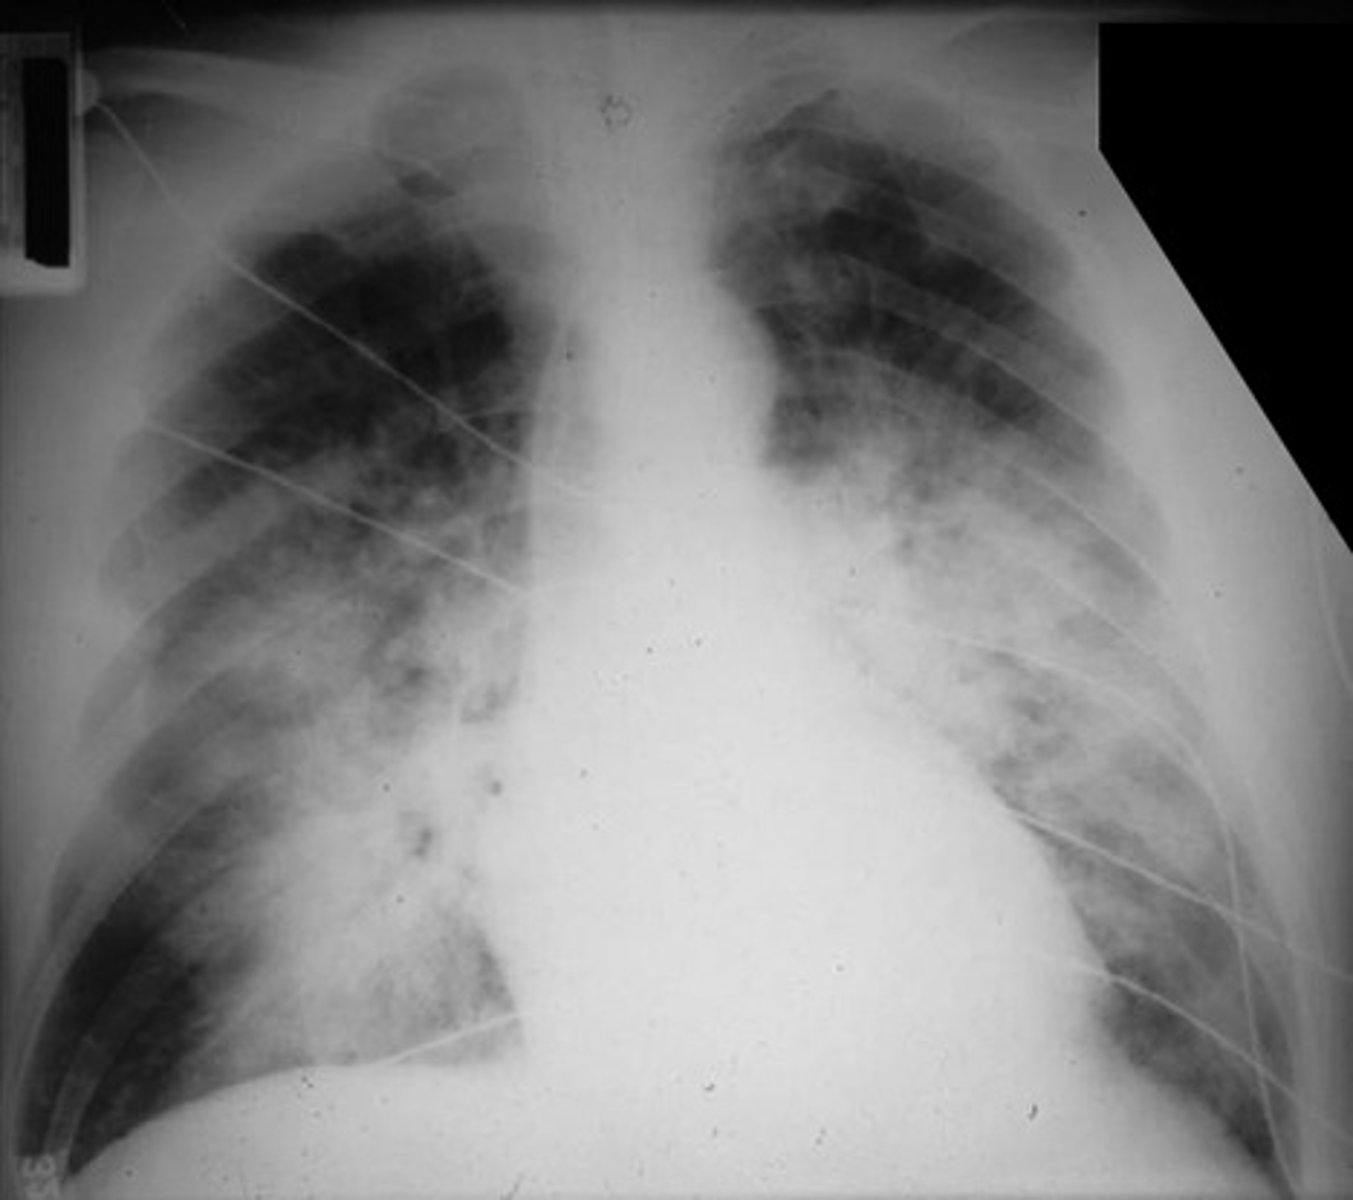

ARDS

Bilateral interstitial infiltrates